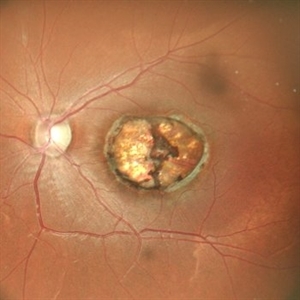

SCARRED CHOROIDAL NEOVASCULAR MEMBRANE

FUNDUS PHOTOGRAPH OF AN 18 YEAR OLD MALE WITH A SCARRED CHOROIDAL NEOVASCULAR MEMBRANE

Photographer: Dr. Akansha Sharma-Retina Foundation, Ahmedabad

Condition/keywords: choroidal neovascularization (CNV), CNVM